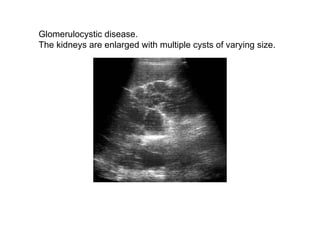

Glomerulocystic disease.  The kidneys are enlarged with multiple cysts of varying size.